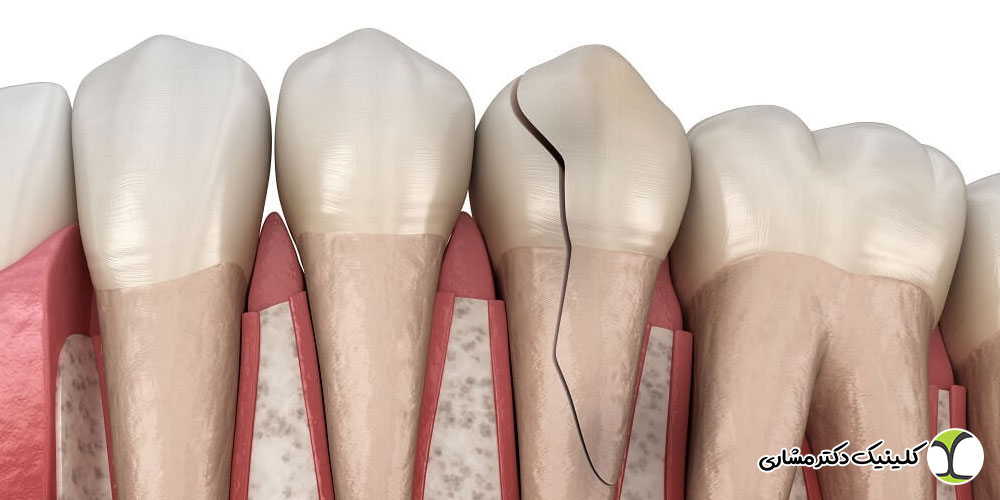

عفونت ریشه زمانی رخ میدهد که پالپ دندان – بافت زنده داخل کانالهای ریشه – بر اثر باکتریها ملتهب یا دچار نکروز شود. این وضعیت معمولاً نتیجه پوسیدگی عمیق، شکستگی دندان، ضربههای دندانی یا درمانهای ناقص قبلی است. از آنجا که پالپ در عمق دندان قرار دارد، تشخیص قطعی عفونت بدون رادیوگرافی تقریباً غیرممکن است.

بررسی خطوط شکستگی ریشه: در برخی موارد، شکستگیهای طولی یا میکرودرجهای ریشه باعث نفوذ باکتریها و عفونت میشوند. رادیوگرافی کمک میکند این شکستگیها شناسایی شوند.